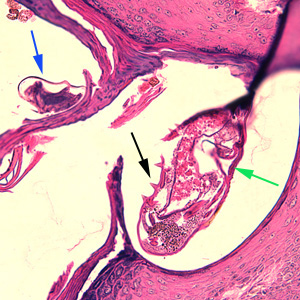

Case #244 – January, 2009

An 80-year-old resident of a long-term care facility presented with a skin condition manifesting as thick crusts over the skin accompanied by slight itching. The patient was originally treated for impetigo, with no resolution, and was ultimately admitted to the hospital for further testing. A skin biopsy was performed. The specimen was sectioned, stained with hematoxylin and eosin (H&E) and sent to a dermatopathologist for diagnostic assistance. Figures A–D show what was observed in the stained sections. Figures A and B were taken at 200x magnification. Figures C and D represent the same fields, respectively, taken at 400x magnification. What is your diagnosis? Based on what criteria?

Figure B